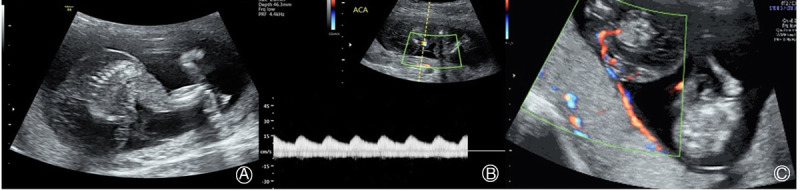

Twin reversed arterial perfusion sequence, a severe and unique complication of monochorionic multiple pregnancy, is characterized by vascular anastomosis and abnormal or absent cardiac development in the twins. This article reviewed its pathogenesis, prenatal ultrasound diagnosis, and management. The pump twin's chances for survival can be maximized by proper management. The optimal timing of the interventions remains a debate, although the latest studies encourage early intervention, i.e., in the first trimester. The most preferred approach is to interrupt the vascular supply to the acardius, such as through ultrasound-guided laser coagulation and radiofrequency ablation of the intrafetal vessels.